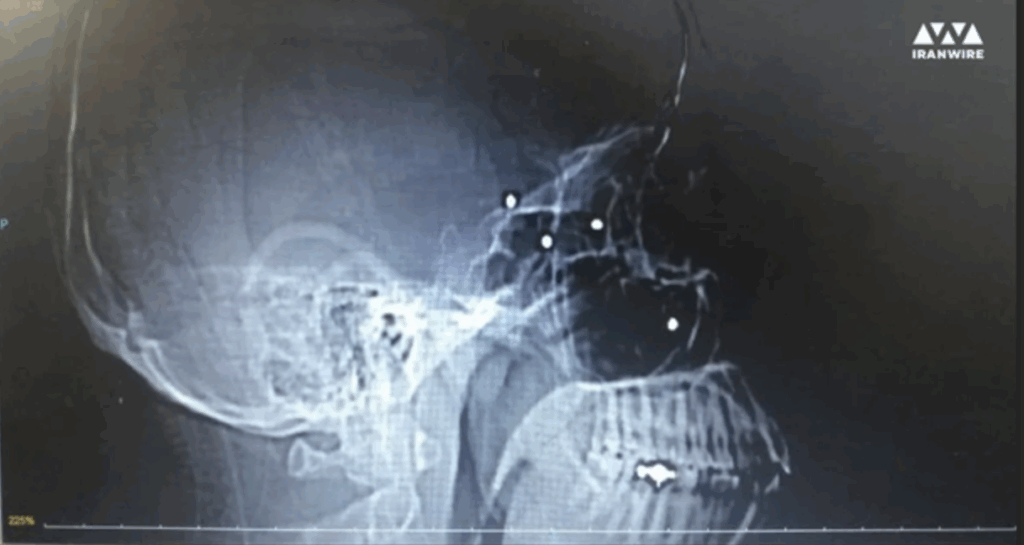

برای تهیه این گزارش، پروندههای پزشکی شماری از آسیبدیدگان چشمی با گروهی از چشمپزشکان متخصص در نقاط مختلف جهان به اشتراک گذاشته شده است. نتایج بررسیها حاکی از آن است، که الگوی آسیبهای چشمی دلالت بر شلیکهای هدفمند دارد. این متخصصان همچنین تأکید کردهاند، که پیامدهای روانی نابینایی با تجربه ابتلا به سرطان قابل مقایسه است، که شدت خسارات جسمی و روانی ناشی از این نوع سرکوب را بهروشنی نشان میدهد.

پروندههای پزشکی شمار زیادی از قربانیانی که بر اثر اصابت گلولههای ساچمهای به سر و چشم مجروح شدهاند، نشان میدهد که شلیک از فاصله نزدیک انجام گرفته است. یکی از این موارد، حسین، مردی میانسال است که هر دو چشم خود را از دست داد و برای همیشه نابینا شد. در پرونده پزشکی او وجود دستکم ۳۰۰ ساچمه در اطراف چشمهایش ثبت شده است. در زمان حادثه، او به همراه همسرش در مراسم چهلم حدیث نجفی در کرج شرکت کرده بود. شواهد پزشکی و روایتهای شاهدان نشان میدهند، که حسین در حالی که بیحرکت بر زمین افتاده و تسلیم شده بود، با شلیک تفنگ شاتگان هدف قرار گرفت.[۹۴] حسین به دلیل نگرانی از انتقامجویی حکومت ایران ترجیح داده است، که هویت خود را ناشناس نگه دارد.